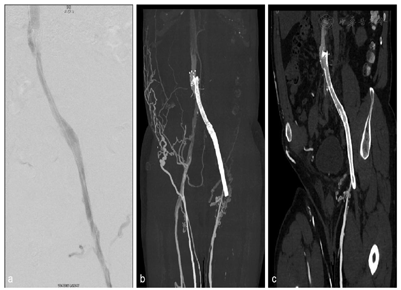

双下肢静脉CTV像示左侧髂外静脉-髂总静脉-下腔静脉支架留置影,左侧髂外静脉远端可见少许对比剂充盈,余支架管腔内可见低密度充盈缺损影,左侧髂外静脉、髂总静脉未见对比剂充盈;左侧腹股沟可见多发侧支血管显影,左侧腹壁内侧-左肾静脉侧支血管建立影像(图1,图2),右侧髂外静脉、髂总静脉及下腔静脉可见对比剂充盈,密度不均匀;双足、双下肢皮下多发迂曲静脉显影,双侧大隐静脉充盈良好,左侧股静脉近端充盈缺损,血管纤细,密度不均(图1)。诊断:左侧髂外静脉-髂总静脉-下腔静脉支架留置,支架内血栓形成,左侧腹股沟区、左侧腹壁内测-左肾静脉及腹壁静脉建立。介入治疗后复查双下肢静脉CTV,可见左侧大隐静脉开口以近支架内血管大致通畅,支架以远端下肢静脉未见明确显影,左侧腹股沟区侧支循环较前减少,左侧腹壁内侧-左肾静脉侧支血管较前减轻(图3、图4)。

下肢静脉栓塞的诊断金标准为DSA检查[1],但DSA是有创检查,准备时间长,耗费人力物力,同时DSA存在过量辐射暴露风险且检查费用较高,检查过程中易损伤血管壁导致新鲜血栓形成[2,3,4]。对比DSA,CT血管检查操作简便,显影效果好,安全微创,对比剂用量少,成像范围大,辐射剂量低。根据对比研究,可以准确评估下肢静脉的通畅性,能展现整个下肢静脉系统情况及静脉栓塞疗效评估,与DSA吻合度高。双源CT低kV高mAs球管技术,在降低患者辐射剂量前提下,增强了碘对比剂衰减,在CT血管检查中用低流速低对比剂用量亦可获得高质量的CT血管诊断图像。本例双下肢CTV采用90kV,双筒双流速度2.5ml/s直接注入下肢静脉各100ml混合剂(造影剂10%+盐水90%),可获得可观的静脉血管图像(图1)。对比常规CT(120kV),低kV技术大幅度降低辐射剂量。此外,CT血管后处理灵活方便,结合探针分析,更是可以细节、清晰地观察支架内外管腔及管壁情况(图2、图3),为临床诊断提供准确的影像学资料,为患者病变及时发现及进一步治疗提供可靠依据[5]。CT作为微创检查方式,"三低"双下肢CTV可常规应用,替代传统120kV,满足临床诊断需求同时提高患者的舒适度,降低辐射剂量,减少并发症,并适合血栓患者术前明确诊断及术后疗效评估(图4)。为了实现常规低kV血管成像,其他先进的技术也被使用,如CARE Dose4D(实时自动曝光控制)和ADMIRE(高级模型迭代重建)。在本病例中,有效剂量仅为0.65mSv。